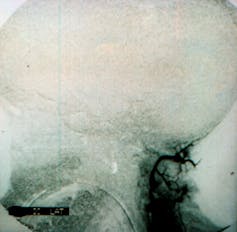

Para ello, es imprescindible constatar, mediante una exploración clínica, que ha cesado completa e irreversiblemente toda actividad neurológica de base intracraneal, incluyendo la respiración espontánea. También debe comprobarse el cese de la actividad eléctrica del cerebro (mediante un electroencefalograma) o del flujo sanguíneo cerebral (empleando arteriografía cerebral, sonografía Doppler transcraneal o pruebas equivalentes).